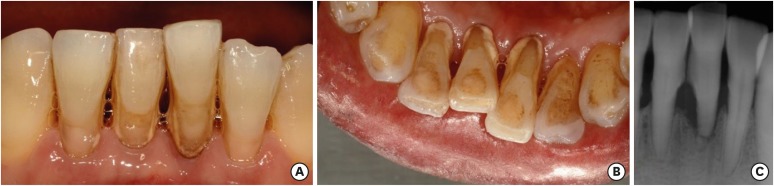

The pontic and abutment teeth were in good condition at an 8-month recall examination. No specific discomfort was reported, although some calculus was present on the mandibular anterior tooth. Periapical radiography was taken and it showed bony healing of the extraction socket (Figure 13).

Figure 13

At an 8-month recall check.